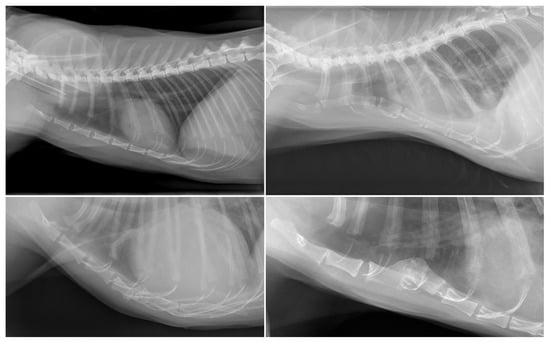

| Shape deformity (n = 24) | Pectus excavatum (n = 6) | Pug (2/7); Boxer (1/13); Dachshund (1/19); French Bulldog (1/23); mixed (1/145) |

| Pectus carinatum (n = 18) | French Bulldog (8/23); Chihuahua (5/28); mixed (3/145); Pug (1/7); Welsh Springer Spaniel (1/3) | |

| Shape deformity (n = 8) | Pectus excavatum (n = 6) | Domestic Shorthair (6/112) |

| Pectus carinatum (n = 2) | Domestic Shorthair (1/112); Norwegian Forest (1/4) | |